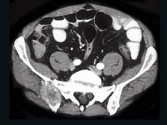

- 单项选择题男,59岁, 右侧髋骶部持续性疼痛,夜间加重, 2月前被确诊为肾细胞癌,结合图像, 最可能的诊断是 ( )

D、骨转移瘤